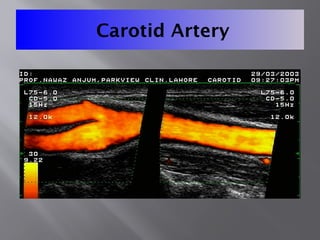

Carotid Artery